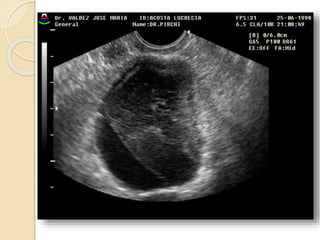

Quistes Endometrósicos:

Clínicamente se manifiesta por dismenorrea,

dispareunia e infertilidad.

La lesion mas detectable por la imágenes esta

constituida por los quistes endometrosicós

(endometriomas) que se forman a partir de los

implantes ováricos configurando los quistes

“achocolatados”.

Se observan quistes de paredes relativamente

gruesas e irregulares con débiles ecos en su

interior debido al contenido hemático.

Quistes Endometrósicos: Clínicamentese manifiesta por dismenorrea, dispareunia e infertilidad. La lesion mas detectable por la imágenes esta constituida por los quistes endometrosicós (endometriomas) que se forman a partir de los implantes ováricos configurando los quistes “achocolatados”. Se observan quistes de paredes relativamente gruesas e irregulares con débiles ecos en su interior debido al contenido hemático.